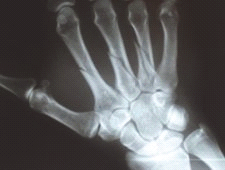

Na radiogramie uwidoczniono złamanie

A. I, V kości śródręcza.

B. paliczków palców II, III, IV.

C. II, III, IV kości śródręcza.

D. paliczków palców I, V.